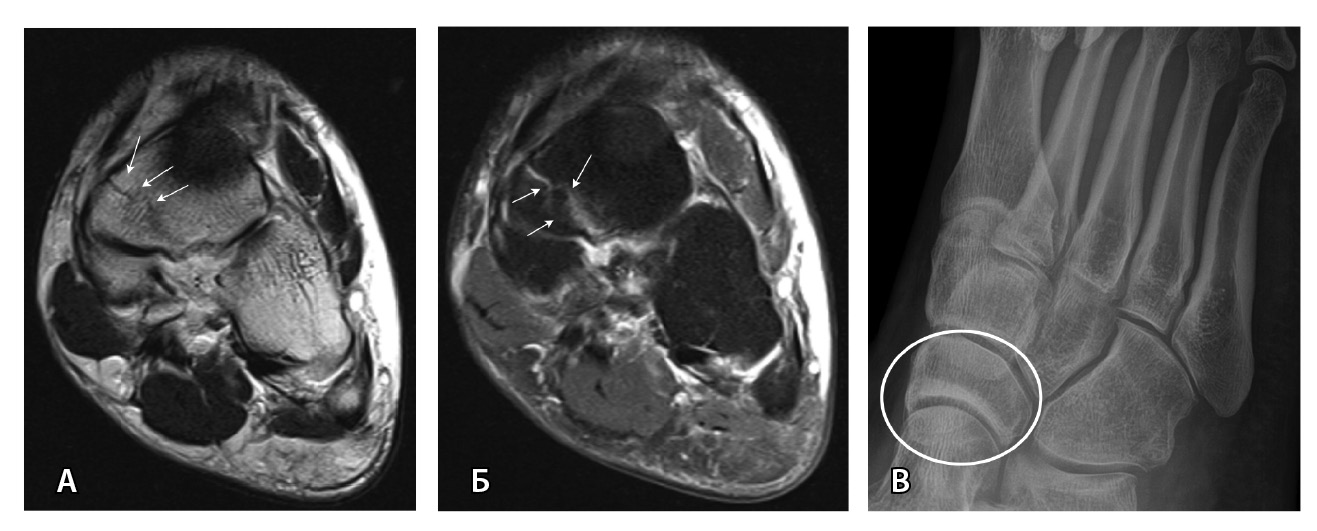

МРТ – наиболее подходящий метод визуализации остеохондрального повреждения купола таранной кости с чувствительностью и специфичностью 96% [52]. В исследованиях M. Haubro и соавт. [53], M. P. Wilson и соавт. [28] МРТ квалифицирована как золотой стандарт диагностики скрытых переломов по сравнению с КТ и рентгенографией. Протокол, состоящий из корональных T1-взвешенных изображений и STIR, обладает 100% чувствительностью в выявлении рентгеннегативных переломов (рис. 3) [28].

МРТ – первоначальный метод диагностики при подозрении на стрессовые переломы, так как ранним признаком таких переломов служит отек костного мозга пораженной кости, ярко выделяющийся среди остальных неизмененных костей. Отсутствие визуализации костного мозга затрудняет диагностику такого рода повреждений при рентгенографии и КТ (рис. 4). Чувствительность МРТ в выявлении стресс-переломов достигает 99% (95–100%), а специфичность – 97% (88–100%). Несмотря на то что исторически сцинтиграфия была основным методом обнаружения стресс-переломов с почти 100% чувствительностью, в настоящее время выполнение радионуклидного метода не рекомендуется из-за его низкой специфичности и высокой дозы ионизирующего излучения [54].